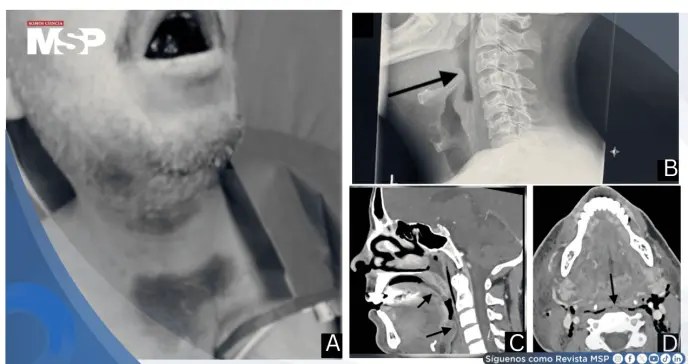

A su llegada, el paciente se encontraba incapaz de recostarse. El examen físico reveló múltiples equimosis en región supraesternal, cuello y áreas submandibulares, con edema y coloración violácea de la lengua.

La radiografía lateral de cuello demostró edema difuso del piso de la boca y área epiglótica con oclusión casi completa de la hipofaringe.

La tomografía computarizada de cuello realizada posteriormente confirmó edema extenso de tejidos blandos con compresión significativa de orofaringe e hipofaringe.